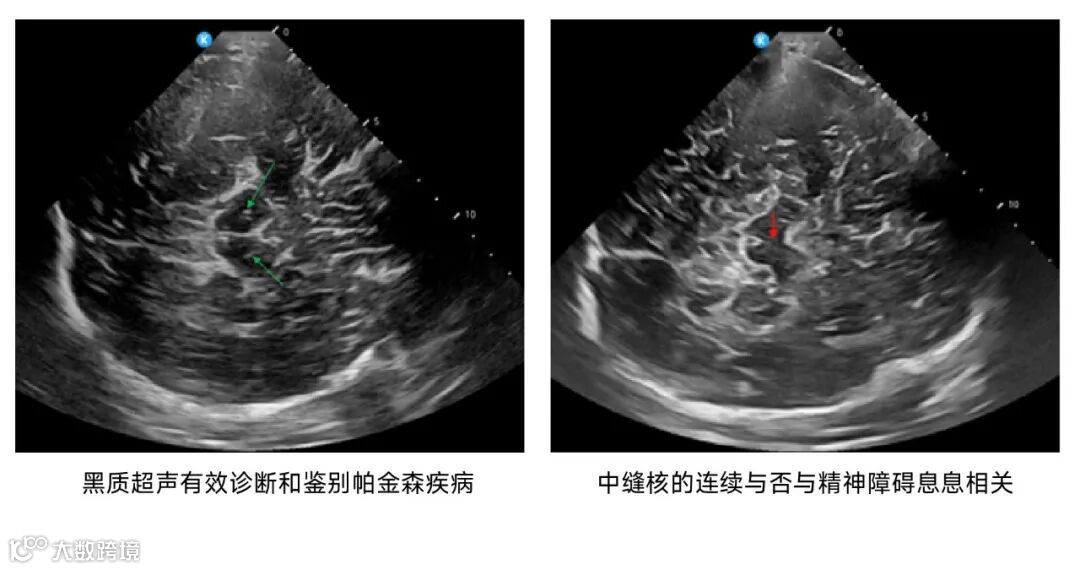

鲲为科技基于kOS带来的超分辨成像技术和超穿探头,

进一步拓展了颅脑超声的应用场景,

在神经内科、神经外科、神经重症监护监测、急诊重症监护、儿科及神经调控等领域带来革命性的创新诊断方案。